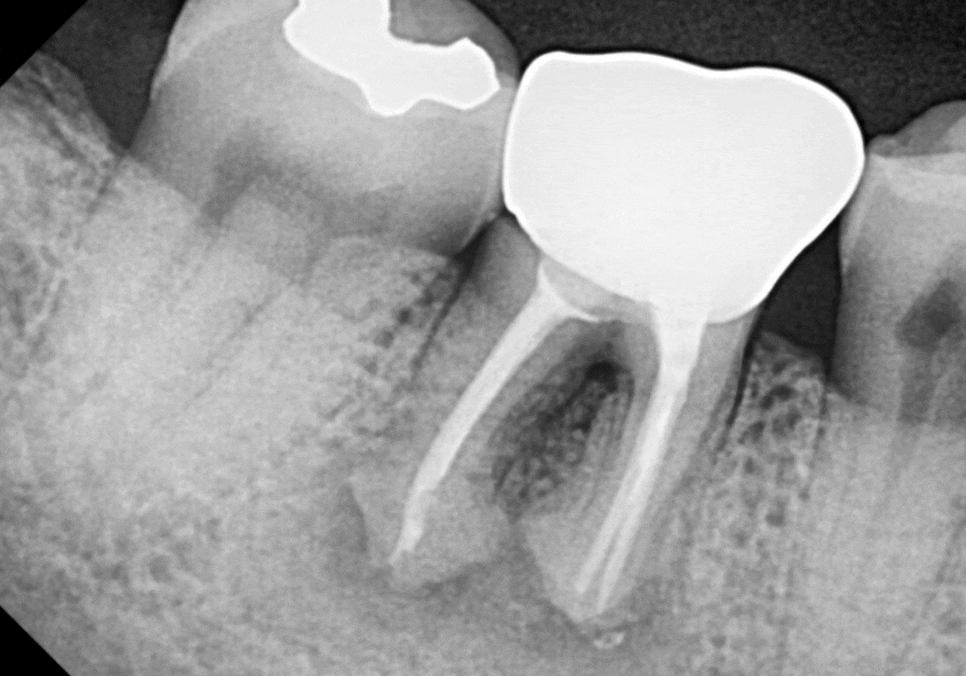

이 환자분도 발치 후 부족한 공간을 채워줄

'뼈이식'을 먼저 진행했습니다.

녹아내린 자리에 뼈이식 재료를 채워 넣어

임플란트를 든든하게 지지해 줄

땅을 만든다고 생각하면 됩니다.

이 환자분도 뼈이식 후

약 3개월 정도 충분히 기다린 뒤,

뼈가 형성된 것을 확인하고

임플란트 뿌리를 심었습니다.

환자분은 4개월 정도 더 기다리며

임플란트와 뼈가 단단히 하나가

되기를 기다렸습니다.

짐작이 아닌 수치(데이터)로 유착 정도를

정확히 확인한 후 최종 보철물을 완성해 드렸습니다.